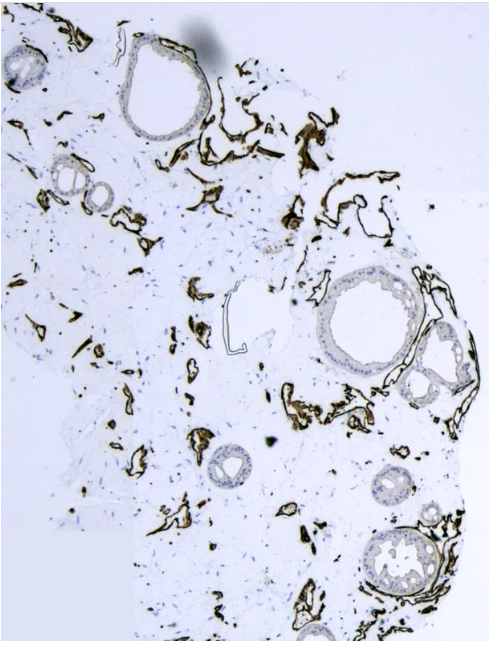

该装置 的微流控平台,可用于在体外培养多达 128 个立灌注和血管化的结肠类器官。与传统的微流体装置不同,具有“开孔”设计的血管化类器官芯片装置不需要任何外部泵系统,并且允许提取组织用于下游分析,例如组织化学甚至体内移植。通过优化细胞外基质(ECM)和培养基配方,患者来源的结肠类器官在自组装血管网络中成功共培养,并且发现在持续灌注下,结肠类器官在平台中生长明显更好与传统的静态条件相比。此外,使用该平台开发了具有先天免疫功能的结肠炎症模型,其中可以从脉管系统招募循环单核细胞,分化为巨噬细胞,并渗透结肠类器官以响应肿瘤坏死因子(TNF)-炎症细胞因子的刺激。凭借在血管内灌注下生长血管化结肠类器官的能力,该装置 平台可以为筛选潜在治疗靶点或建模相关疾病带来新的可能性。

血管化结肠类器官

通过优化细胞外基质 (ECM) 和培养基配方,该装置成功地在自组装血管网络内共培养患者来源的结肠类器官。与传统静态条件相比,我们的平台已被证明可以在持续灌注下显着改善

类器官的生长。该装置还可以利用先天免疫功能对结肠炎症进行建模。循环单核细胞可以从脉管系统中招募,分化为巨噬细胞,并响应 TNF-α 炎症细胞因子的刺激而渗透结肠类器官。